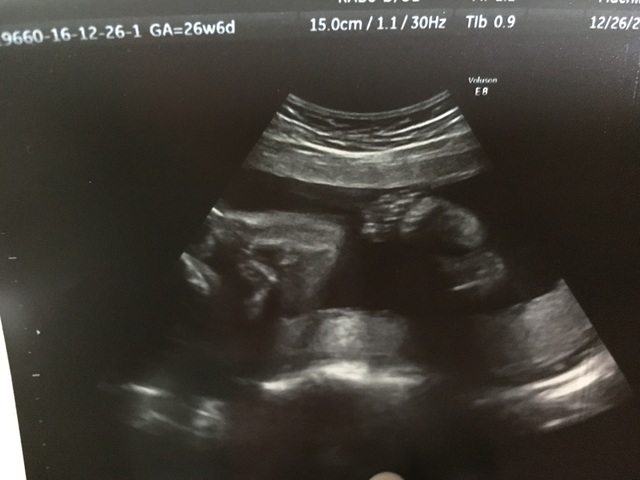

26週0日(26w0d・男の子)|さやたん さん(28歳)

エコー写真撮影時のエピソード:

やっと顔の目鼻口が出来てきたところを、アップでエコー写真を撮ってくださいました。 口などに障害とか出る場合はこの時にわかるみたいです。

何事も無くて、安心したのを覚えてます。 左腕で顔を隠そうとしている写真でした(^^)